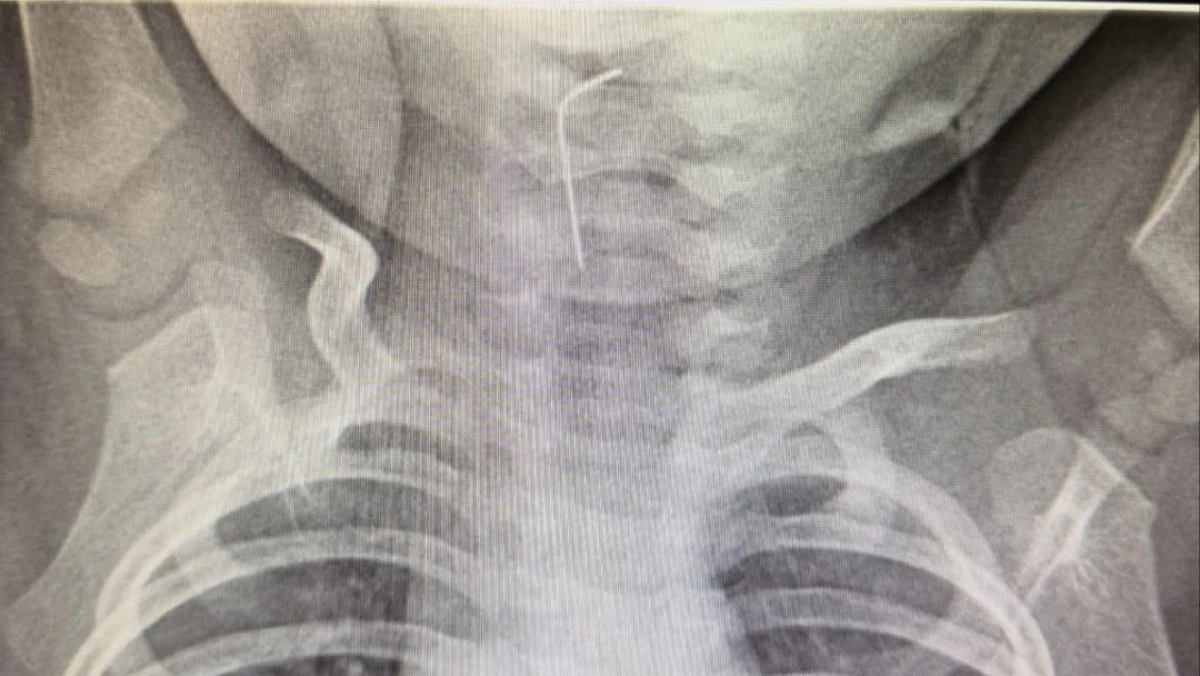

Түркістан облыстық балалар ауруханасына жедел жәрдем қызметі арқылы 9 айлық сәби шұғыл түрде жеткізілді, деп хабарлайды Paryz.kz.

Фото: әлеуметтік желіден

Белгілі болғандай, сәби абайсызда ине жұтып қойған.

«Тез арада аурухана мамандары - хирург Темірбеков Мұхагали және эндоскопист Ырысқұлов Бабыр эндоскопиялық әдісті қолдана отырып, рентгенологиялық тексеру жүргізді. Нәтижесінде бөгде заттың нақты орналасқан орнын анықтап, өңеште тұрып қалған бөгде затты сәтті түрде алып шықты», - деп хабарлады Түркістан облысы әкімдігінің баспасөз қызметі.

Медициналық көмек жедел әрі кәсіби көрсетілуінің нәтижесінде ықтимал асқынулардың алдын алу жұмыстары сәтті аяқталды. Дәрігерлердің айтуынша, қазіргі таңда баланың жағдайы жақсы. Сәби дәрігерлердің бақылауында болып, үйіне шығарылды.